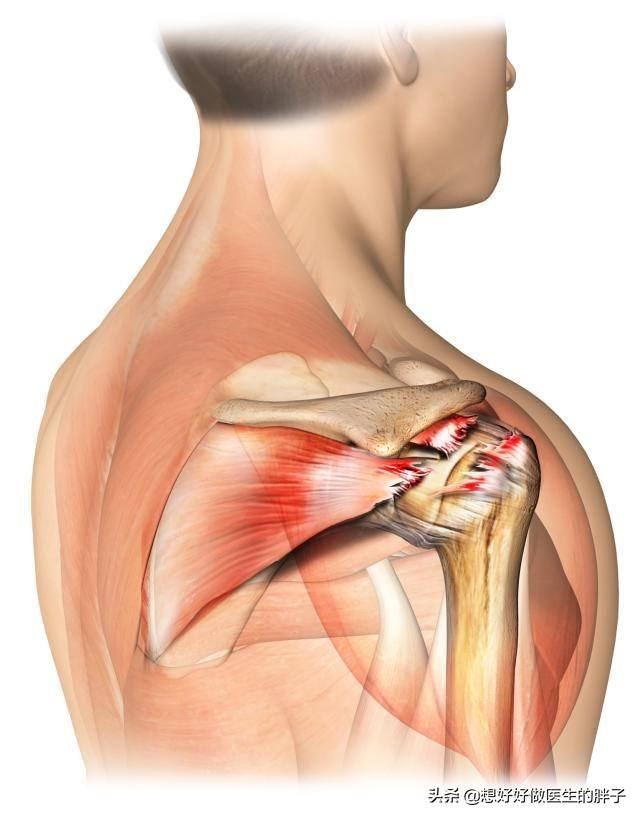

Lorsque je vous ai parlé du syndrome de l'impaction de l'épaule, j'ai mentionné en passant la coiffe des rotateurs.Les coiffes des rotateurs sont également appelées coiffes des rotateurs.qui joue un rôle très important dans le mouvement de l'articulation de l'épaule. Il est principalement constitué de 4 tendons réunis, sur leComme les 4 doigts d'une main qui saisissent la tête humérale de l'articulation de l'épaule afin que la tête humérale puisse se déplacer dans toutes les directions.。

Cependant, l'utilisation prolongée de l'articulation traumatisée de l'épaule et le syndrome de l'impaction de l'épaule peuvent entraîner diverses causes de lésions du tendon.dégénérescence和l'usureLe patient aura unedouleur à l'épauleIl existe également une légère adhérence de l'épaule lorsqu'elle est secondaire à une inflammation aseptique de l'articulation de l'épaule, mais elle n'est pas induite comme le syndrome de l'impingement de l'épaule, ou bien elle n'est pas induite.Limite rarement l'amplitude des mouvements de l'ensemble de l'articulation.。

Les zones fréquemment douloureuses ou les muscles affectés sont le deltoïde, le pectoral mineur, l'infra-épineux, le supra-épineux, le vaste latéral, le latissimus dorsi, le biceps et la bourse de la coiffe des rotateurs.Les points de pression se situent principalement au niveau des attaches os-tendon.或Sur les points sensibles des nerfs innervant ces muscles, on peut sentir à la palpation qu'ils sont striés et indurés.